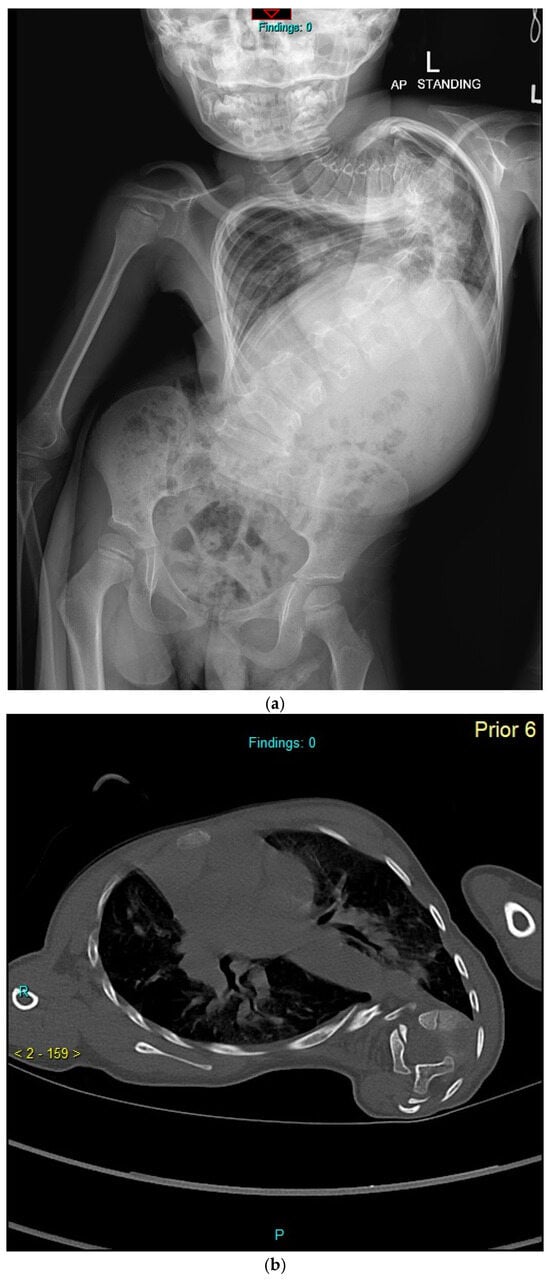

Previously Unreported TMEM38B Variant in Osteogenesis Imperfecta Type XIV: A Case Report and Systematic Review of the Literature

Osteogenesis imperfecta (OI) type XIV is a rare recessive disorder caused by TMEM38B pathogenic variants that disrupt an endoplasmic reticulum protein essential for calcium homeostasis and bone mineralization. This leads to severe bone fragility, early-onset fractures, skeletal deformities, low bone mass, scoliosis, and [...] Read more.

Osteogenesis imperfecta (OI) type XIV is a rare recessive disorder caused by TMEM38B pathogenic variants that disrupt an endoplasmic reticulum protein essential for calcium homeostasis and bone mineralization. This leads to severe bone fragility, early-onset fractures, skeletal deformities, low bone mass, scoliosis, and variable features like blue sclerae or dental abnormalities. We present a case report of a 21-year-old Italian male with a novel homozygous TMEM38B splice variant (c.112 + 1G > T), detailing the clinical presentation, genetic findings, and therapeutic outcomes. The patient exhibited multiple skeletal deformities and showed a moderate response to bisphosphonate therapy (neridronate). In addition, a systematic review of PubMed and Scopus identified 12 relevant studies from an initial set of 82 publications, encompassing data from 56 patients diagnosed with OI type XIV. Unlike classical collagen-related OI, TMEM38B-related OI necessitates genetic screening beyond classical collagen genes (COL1A1 and COL1A2). While bisphosphonates provide some clinical benefit, persistent fractures underscore the need for long-term management and innovative therapies. This case report and systematic review enhance understanding of OI type XIV and underscore the clinical importance of TMEM38B variants in bone fragility disorders. Full article